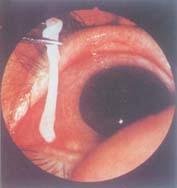

舌形蟲屬的寄生蟲以鉤附著在鼻咽組織,蟲體懸浮在鼻腔中,無全身症狀。其特點是一種急性炎症反應,為非傳染性鼻咽炎。症狀開始於食入含有感染性若蟲的食物後幾分鐘至數小時,以半小時為常見。患者的臨床表現主要為鼻鯉、吞咽困難、發音困難、咽部刺痛,時有氣急,可有顯著的扁桃體肥大、鼻道和嘴唇的水腫。常有鼻腔、淚腺的分泌物,頜下、頸淋巴結有時腫大,臉和頸部有風疹,常見前額部頭痛。

舌形蟲病的診斷在手術、活檢、屍檢、服驅蟲藥後所得蟲體標本,或從鼻腔分泌物、痰和嘔吐物中檢出活蟲便可確診。舌形蟲病也常用X一射線檢查,如從胸片或腹片中見到鈣化的若蟲可作輔助診斷,手術或屍檢在肺、腹部及肝和脾被膜的表面,見到呈不透明直徑0.4~1 cm的C形和月牙形含若蟲包囊的病變。但鈣化的若蟲患者生前一般無症狀,X-射線不能查出未鈣化的若蟲。流行病學調查可用鼻腔拭子和糞便查舌形蟲卵。